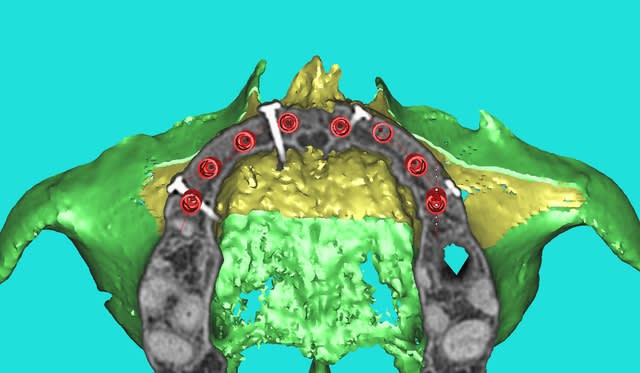

3D secteur 1

Comment simplifier et fiabiliser les greffes cas clinique dr pxav 1 to7kuq - Eugenol

Comment simplifier et fiabiliser les greffes cas clinique dr pxav 2 xckumk - Eugenol

Comment simplifier et fiabiliser les greffes cas clinique dr pxav 4 s9fhn2 - Eugenol

Comment simplifier et fiabiliser les greffes cas clinique dr pxav 5 sp6mxm - Eugenol

Comment simplifier et fiabiliser les greffes cas clinique dr pxav 6 mpweb8 - Eugenol

Comment simplifier et fiabiliser les greffes cas clinique dr pxav 7 o0oczb - Eugenol